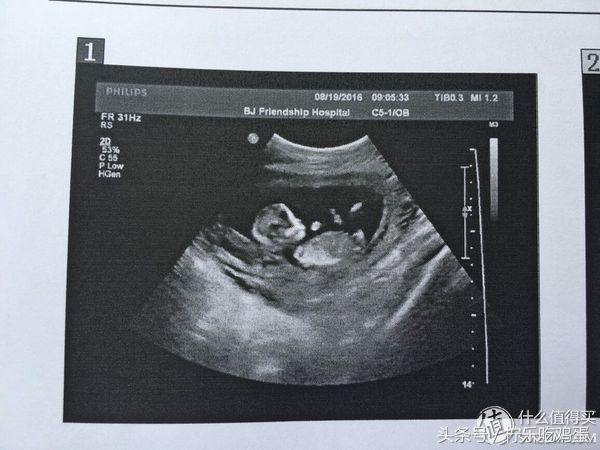

8月19日约的彩超第一次也是唯一一次看清宝宝的全貌